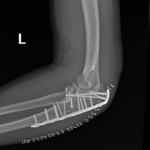

if the fracture is displaced, surgery may be needed to put the bone back into the correct position and fix the bone with Plates & screws or nails for adequate healing to occur.

- Elbow Fractures.